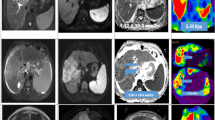

MRE and DWI of focal liver lesions. Examples of hemangioma (top row), focal nodular hyperplasia (second row), hepatocellular carcinoma (third row), and cholangiocarcinoma (bottom row), with representative images from T2-W sequence (first column) and DWI (second column), with corresponding ADC map (third column) and stiffness map from MRE at a similar level. The numerical values over the ADC and stiffness maps are mean ± standard deviation of ADC (10−3 mm2/s) and stiffness (kPa) values of the lesions. Arrows point to the lesions in ADC and stiffness maps

DWI of FLLs

MRE of FLLs

The mean (± SD) stiffness of FLLs was 6.2 ± 3.1 kPa (95 % CI, 5.7– 6.8 kPa). Malignant FLLs showed significantly higher mean stiffness than benign FLLs (7.92 vs. 3.12 kPa, p < 0.001) (Fig. 2). ROC analysis revealed accuracy of 0.98 (p < 0.001) (Table 3), with an optimal cut-off value of 4.54 kPa for differentiating malignant from benign FLLs. One-way ANOVA revealed significant differences among FLLs: HCAs had the lowest mean stiffness (Fig. 3), at less than 4 kPa, which was significantly lower than that for HCCs, CCAs and METs (p < 0.0001). No significant differences in mean stiffness were found among HCAs, HEMs, and FNHs (p = 0.98–0.99). The mean stiffness of HEMs was not significantly different from that of FNHs. Stiffness measurements were less than 5 kPa in all but one HEM, which was a 5 cm complex sclerosing hemangioma with mean stiffness of 6.1 kPa. Mean stiffness values were significantly lower for HEMs than for any of the malignant FLLs (p < 0.001). FNHs showed the highest mean stiffness among benign FLLs, but not significantly different from HEMs or HCAs. With the exception of one case with stiffness of 6.2 kPa, stiffness was less than 5 kPa in all FNHs. Mean stiffness was significantly lower for FNHs compared to all malignant FLLs (p < 0.0001).